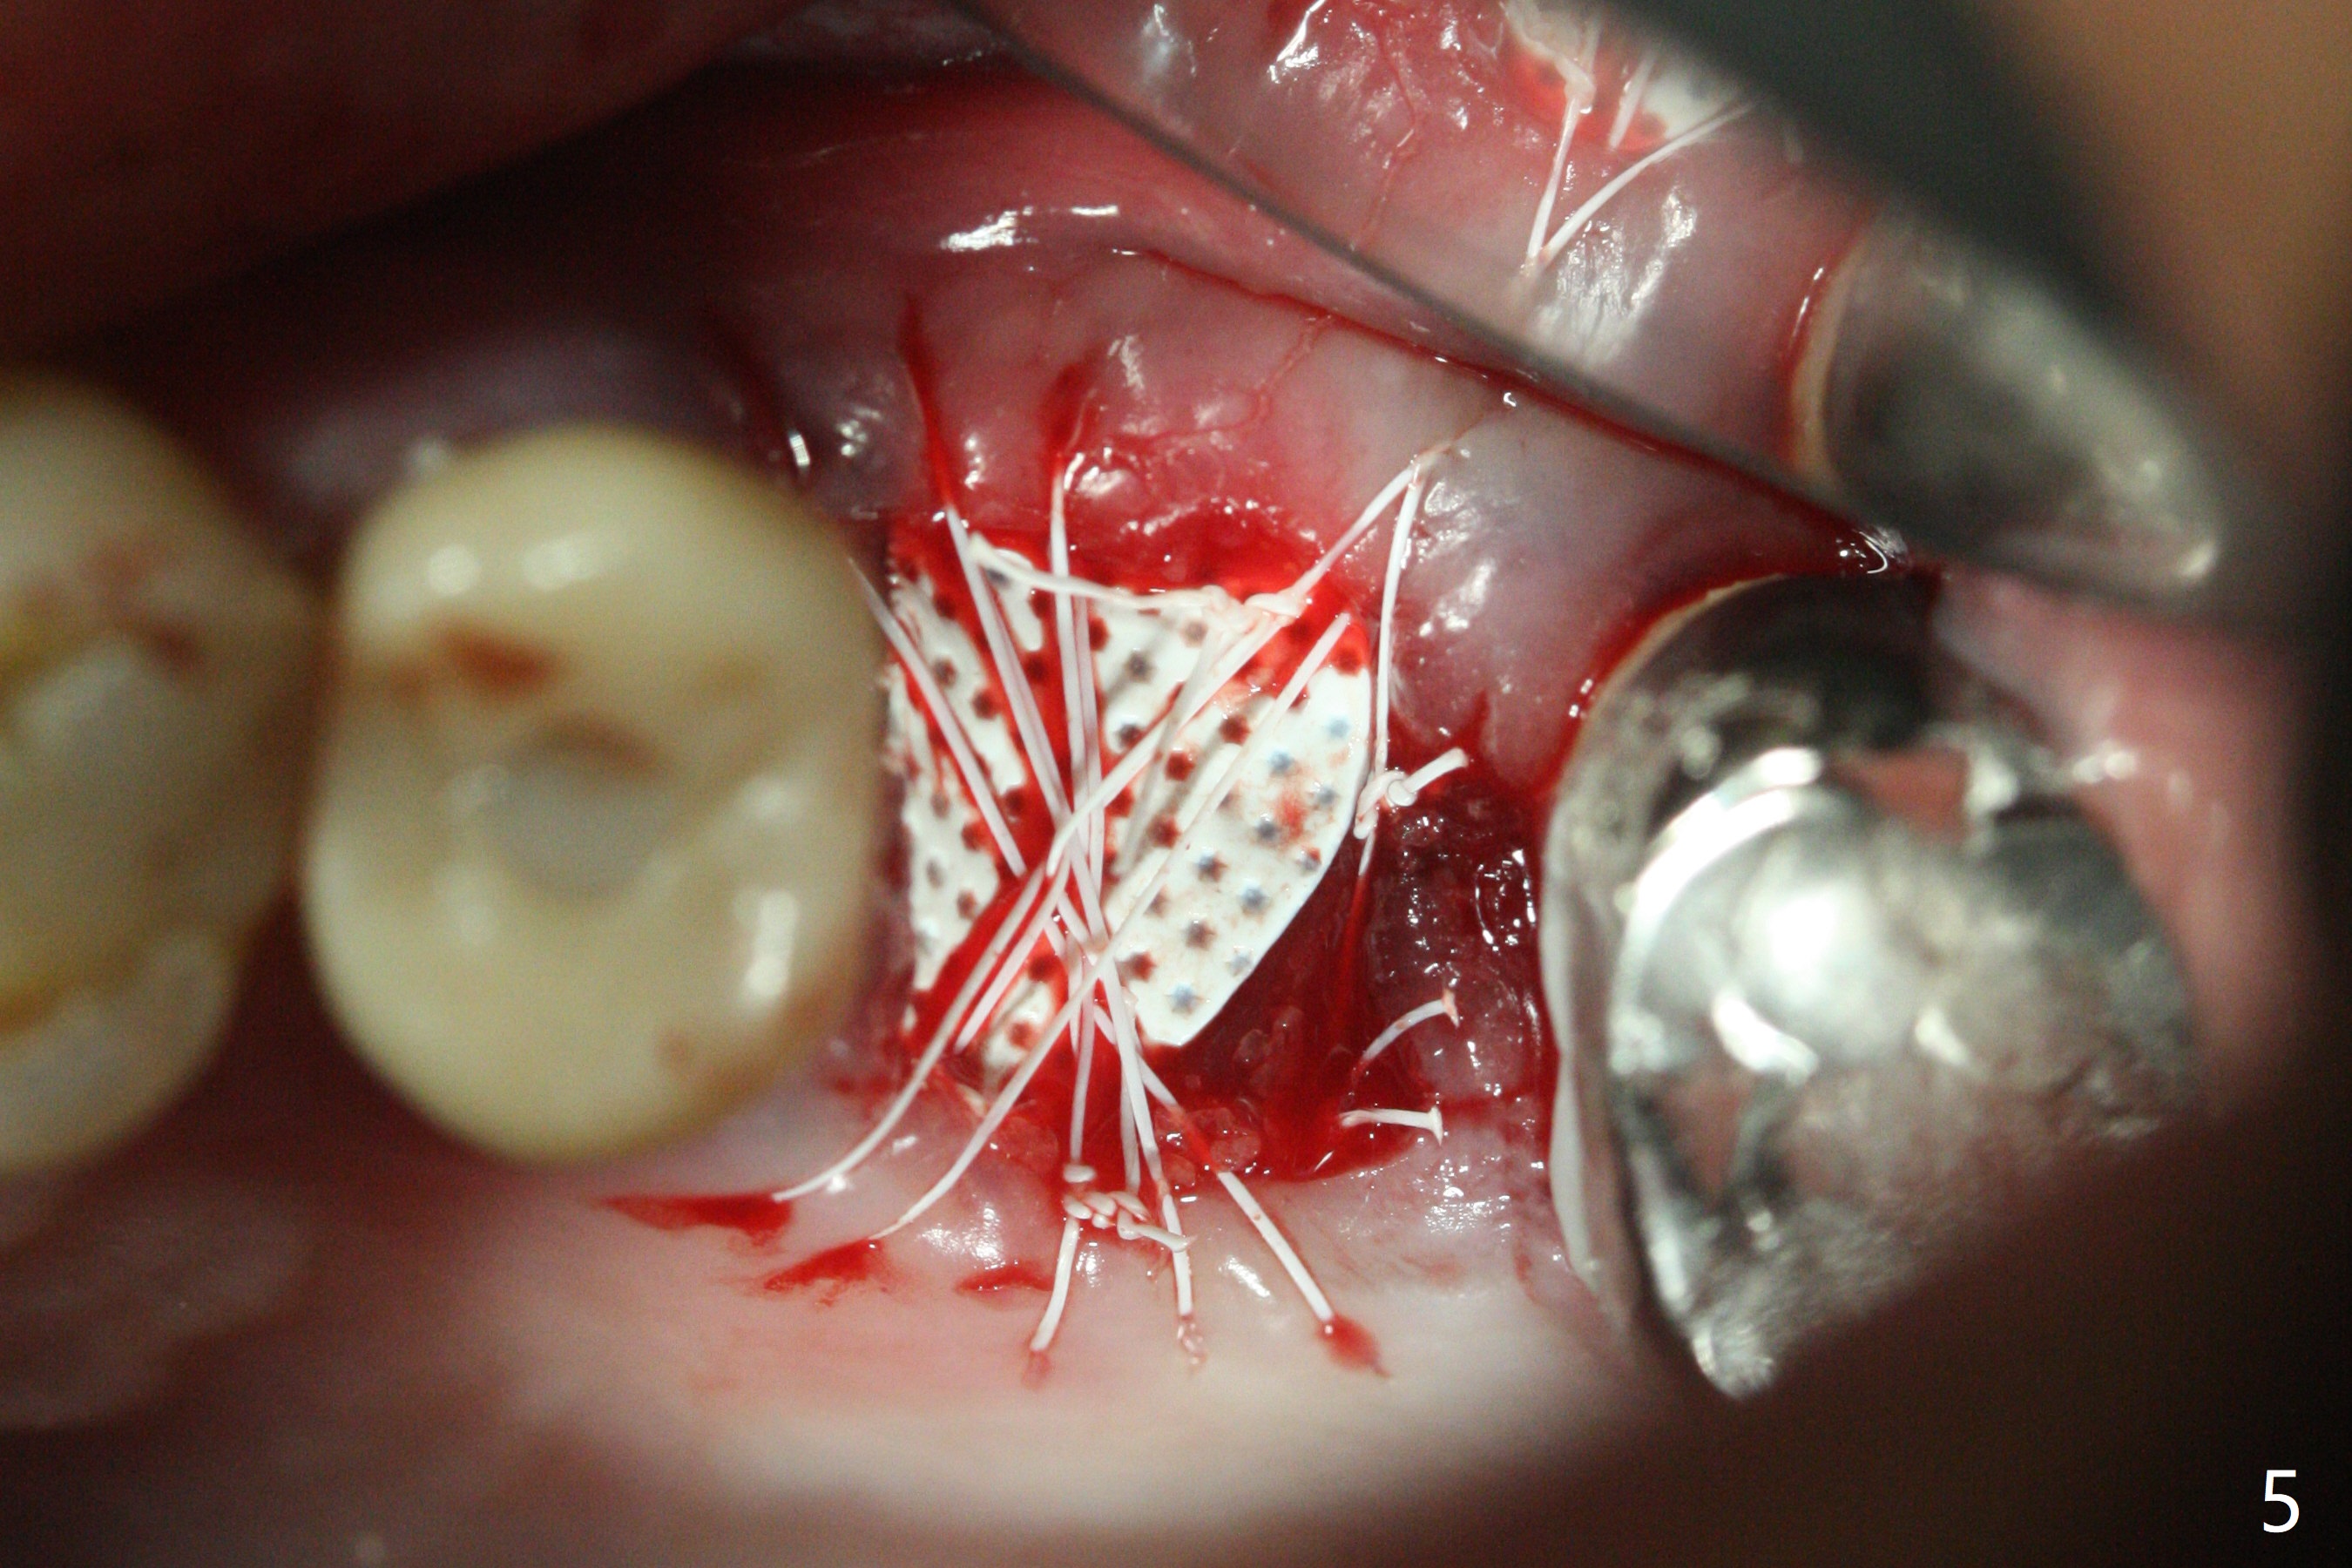

左上六拔除后,近中颊侧窝尤其大,与上颌窦相通(图一 *),而中隔比较尖,截除后还显得窄(图一,二:S),不太适合即刻种植。放置一块PRF膜于近中颊侧窝修补上颌窦,然后放置粘性骨块,好像有上颌窦提升迹象(图三:*(箭头:近中颊侧骨板缺失)),用骨粉填满其余牙槽窝(图四),覆盖另外一块PRF膜以及Cytoplast(不可吸收膜),用PTFE缝线(也不可吸收,与膜是同一个材料,非常柔软,好打结)缝合(图五)。最后使用牙周敷料。后者术后八九天脱落,病人术后十二天复诊,不可吸收膜腭侧有些外翻(图六箭头),伤口愈合尚可,没有骨粉丢失迹象,反复交代口腔卫生。再过三周撤除不可吸收膜。其实三周后膜自己脱落,病人回来撤去剩余缝线(图七),新鲜肉芽组织形成。术后5个月牙槽嵴和角化龈宽,骨高度尚可(图八),密度差些(图九,750单位),植体应该是4.5x8.5 或者 10 毫米,少量上颌窦提升。